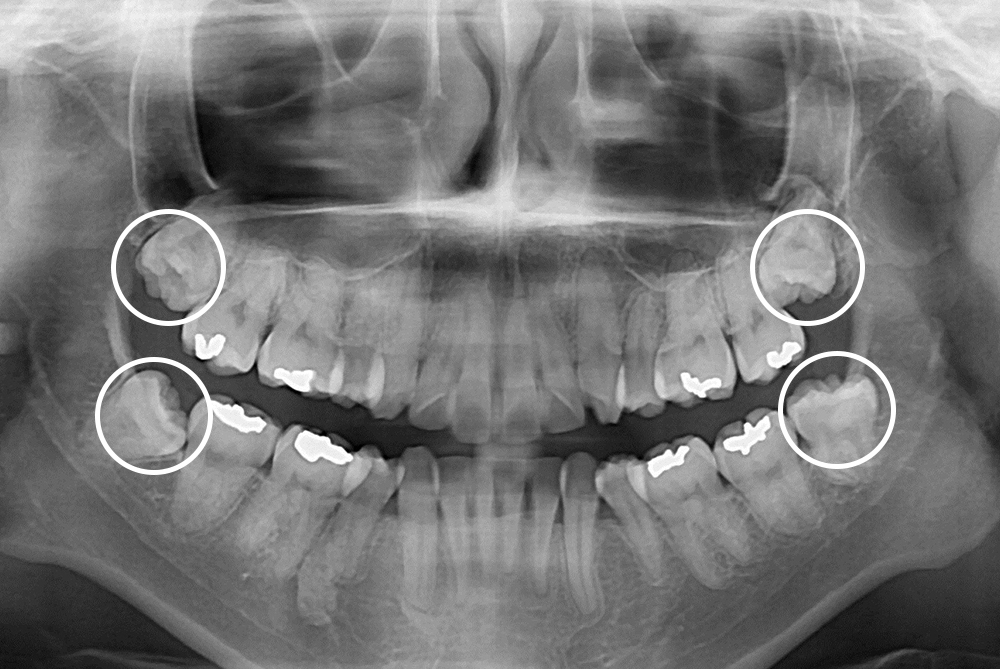

[사랑니] 매복 사랑니 발치

치료전 : 2018-08-27